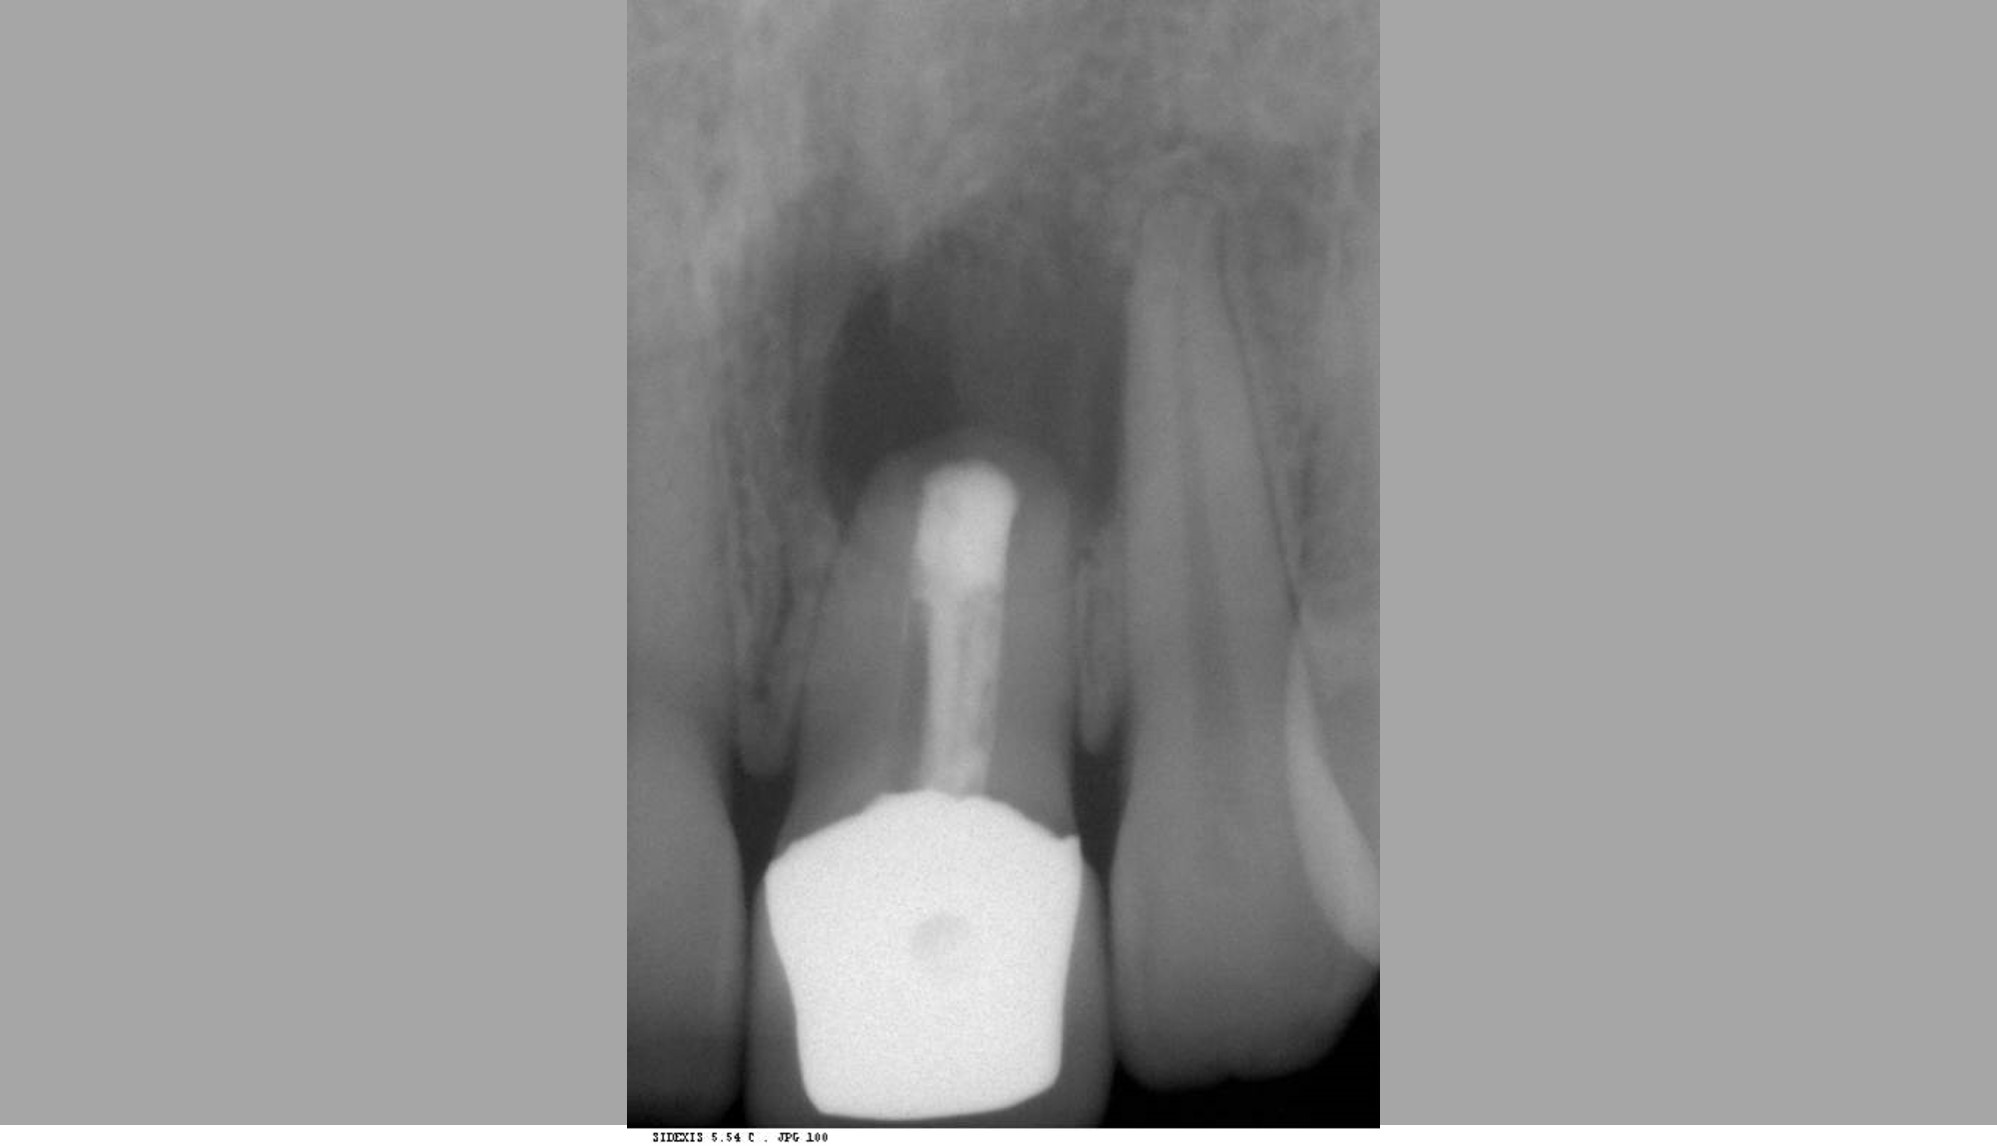

12/12 - Radiographic control five years post-operativeTreatment of dehiscence defect with cerabone® & Jason® membrane - Dr. M. Steigmann